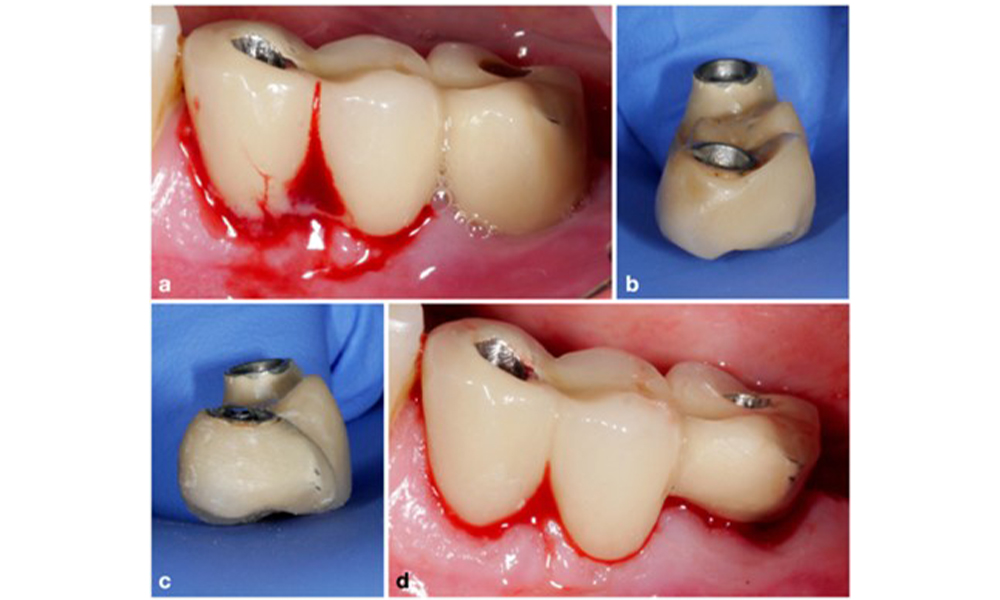

По време на Световния семинар за класификация на пародонталните и периимплантни заболявания и състояния през 2017 г. бяха определени диагностичните критерии за периимплантатен мукозит и периимплантит (Renvert et al. 2018). Периимплантният мукозит се дефинира като (1) наличие на възпаление около импланта (т.е. зачервяване, подуване, линия или капки кръв в рамките на 30 секунди от сондирането), но (2) без допълнителна костна загуба след първоначалното заздравяване (фигура 1 ).

Основният етиологичен фактор за биологичните усложнения около имплантите е оралният биофилм. Ето защо по време на лечението винаги трябва да се вземат предвид два съществени аспекта, независимо от диагнозата периимплантатен мукозит или периимплантит: (1) нивото на орална хигиена и (2) възможността за почистване на протезното възстановяване (фигура 4).

По този начин както ежедневната орална хигиена на пациента, така и дизайнът на протезното възстановяване и позиционирането на импланта трябва да подпомагат ефективното почистване. Ако е необходимо, корекциите на съществуващата реставрация (фигура 5) и специфични инструкции за персонализирана орална хигиена са от изключителна важност (фигура 6) (Hamilton et al. 2023; Jepsen et al. 2015).